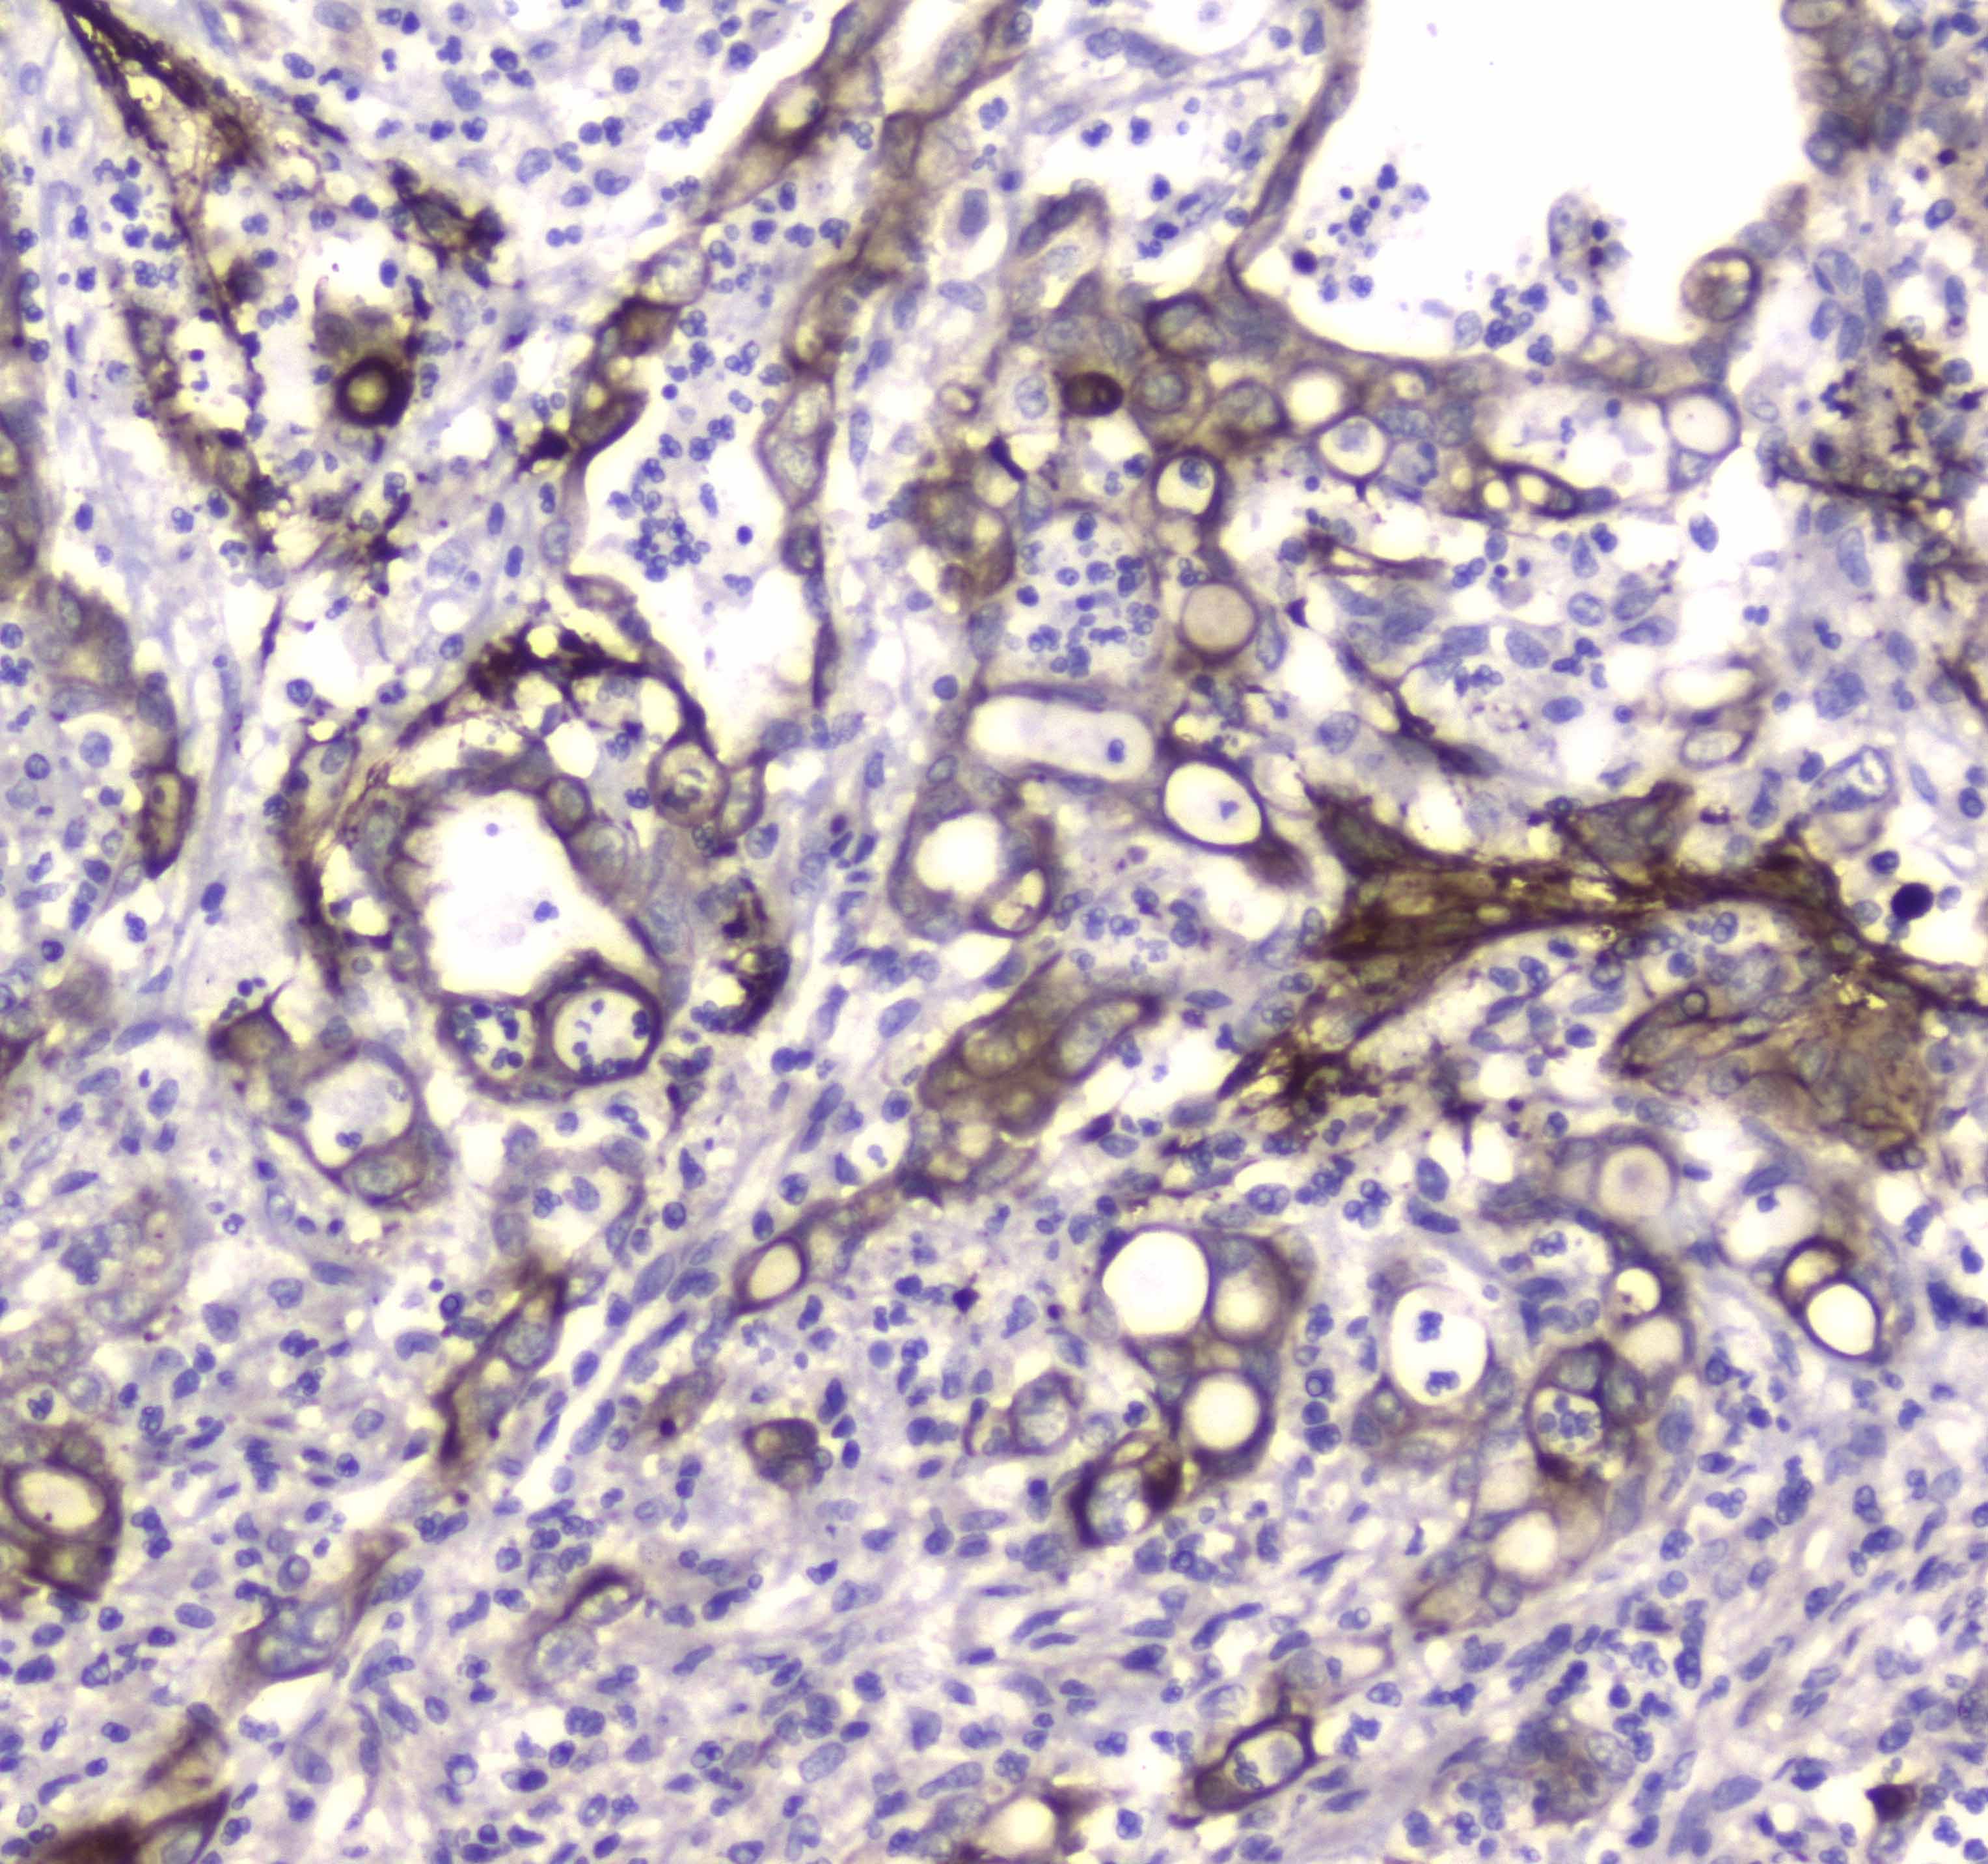

IHC analysis of LC3A/MAP1LC3A using anti-LC3A/MAP1LC3A antibody (A01543-1).

LC3A/MAP1LC3A was detected in a paraffin-embedded section of rat brain tissue. Biotinylated goat anti-rabbit IgG was used as secondary antibody. The tissue section was incubated with rabbit anti-LC3A/MAP1LC3A Antibody (A01543-1) at a dilution of 1:200 and developed using Strepavidin-Biotin-Complex (SABC) (Catalog # SA1022) with DAB (Catalog # AR1027) as the chromogen.